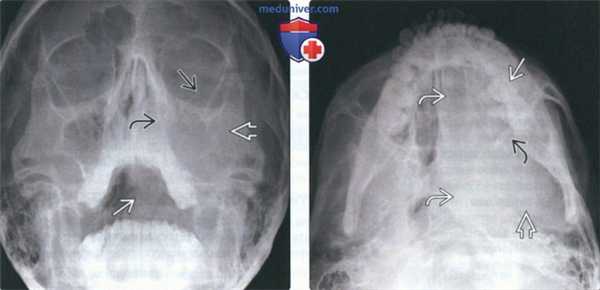

о Злокачественная мелкоклеточная опухоль![Рентгенограмма, КТ, сцинтиграфия при саркоме Юинга челюсти]() (Слева) На рентгенограмме в подбородочно-затылочной проекции в левой верхнечелюстной пазухе определяется неоднородное просветление, продолжающееся книзу к ротоглотке. Медиальная стенка левой верхнечелюстной пазухи неразличима, дно пазухи приподнято.

(Справа) На аксиальной рентгенограмме у этого же пациента определяется просветление в проекции левой верхнечелюстной пазухи полости носа, глотки, основания черепа слева. Задняя стенка верхнечелюстной пазухи четко не визуализируется.2. Рентгенография при саркоме Юинга челюсти:

о МРТ при поражении мягких тканей![Рентгенограмма, КТ, сцинтиграфия при саркоме Юинга челюсти]() (Слева) На рентгенограмме черепа в боковой проекции у этого же пациента определяется затемнение в области носоглотки, обусловленное объемным образованием.

(Справа) На аксиальной КТ с КУ в мягкотканном окне определяется несколько неоднородная мягкотканная опухоль, занимающая левую верхнечелюстную пазуху и носовую ямку, и распространяющаяся в ветвь нижней челюсти и глотку. Нарушена целостность костной стенки верхнечелюстной пазухи.в) Дифференциальная диагностика саркомы Юинга челюсти: 1. Остеосаркома:

• Для дифференциальной диагностики с СЮ необходимо гистопатологическое исследование![Рентгенограмма, КТ, сцинтиграфия при саркоме Юинга челюсти]() (Слева) На аксиальной КТ с КУ в костном окне у этого же пациента определяется опухоль с неоднородной структурой, занимающая левую верхнечелюстную пазуху и носовую ямку, распространяющаяся в ветвь нижней челюсти и глотку. Нарушена целостность костной стенки левой верхнечелюстной пазухи.

(Справа) На сцинтиграмме с Тс-99 МДФ у этого же пациента определяется активная фиксация радиофармпрепарата в верхней челюсти слева и носовой ямке в соответствии с локализацией опухоли, обнаруженной на КТ.1. Общая характеристика: